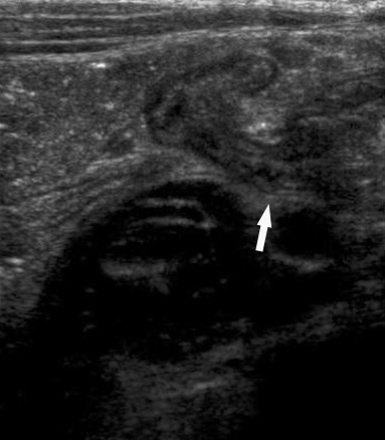

图3 右侧髂窝斜向扫描显示扩张和非扩张肠管的过渡区(箭头)。

一8岁男孩出现急性右侧肋缘疼痛并呕吐。超声显示小肠梗阻。扩张和非扩张小肠肠管临界区位于右侧髂窝(图3),此区域右侧和上方的小部分的小肠肠管堆积受压成胶囊状,蠕动消失(图4)。诊断为腹内疝导致的小肠梗阻。病人而没有再做其他检查进行了手术治疗。